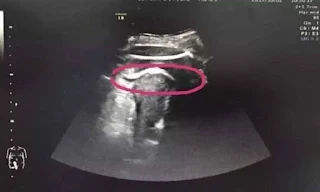

No entanto, eles não esperavam encontrar, durante a ultrassonografia, uma das pernas do bebê fora do órgão. Os profissionais suspeitam que um chute do bebê tenha causado o rompimento, segundo o jornal O Globo. Zhang sofria de forte hemorragia interna e precisou realizar uma cesariana de emergência. Durante a operação, foi confirmado que a perna do feto estava na cavidade abdominal da mãe, através de um corte de sete centímetros.